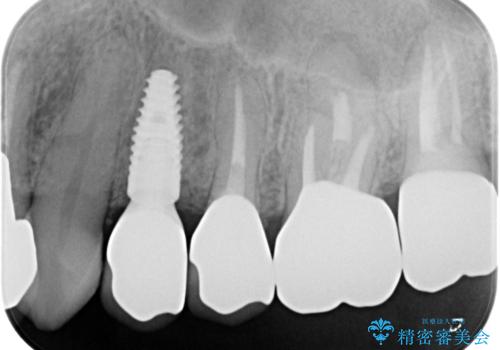

著しく腫れた歯ぐき 歯肉と歯の改善を行う歯周外科

- 最近治療した部位の、ブラッシング時の出血の改善を求め来院されました。

診査により、歯肉と補綴物の調和が取れておらず歯肉が腫れていることが判明し歯周外科で改善していくことを計画します。